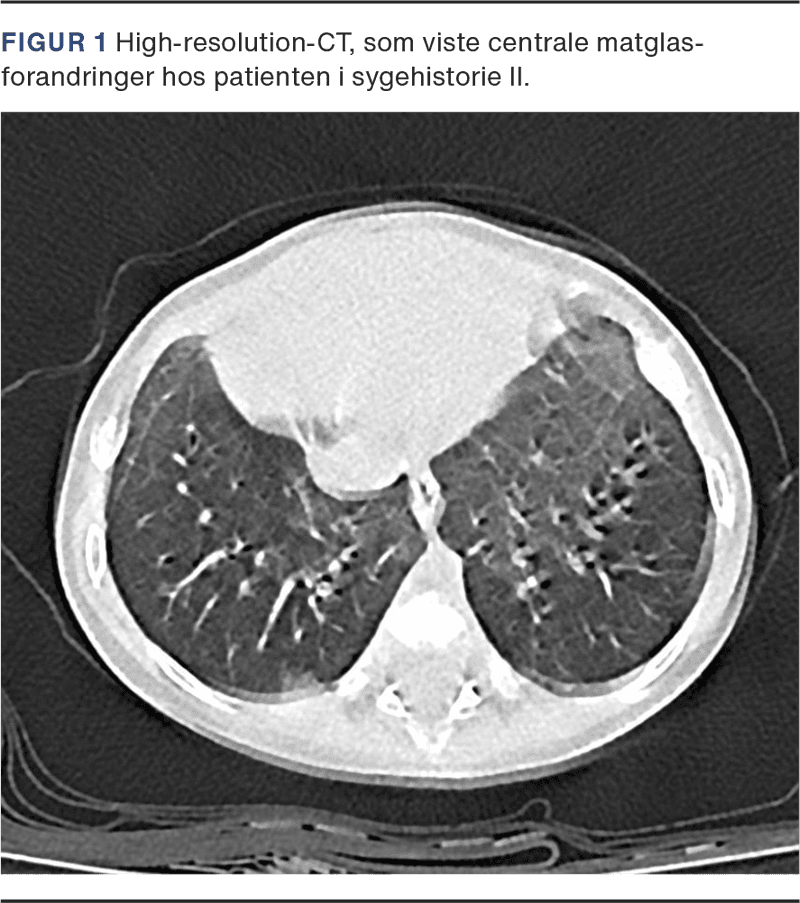

En fem uger gammel matur pige blev indlagt med bronkiolitis, fik behandling med nasal continuous positive airway pressure (N-CPAP) og blev udskrevet efter en uge. Hun blev senere indlagt to gange med bakteriel pneumoni. Røntgen af thorax viste spredte infiltrater og atelektase, som blev behandlet med PEP-maske. Efterfølgende henvendte familien sig gentagende gange, da pigen havde persisterende takypnø og indtrækninger, men var ellers afebril og uden infektionstegn. Der blev målt lav saturation under søvn, og astmamedicin blev givet uden effekt. HRCT viste spredte matglasforandringer bilateralt (Figur 1).

Efter at mere almindelige årsager var udelukket, opstod mistanke om NEHI, og der blev foretaget HRCT af lungerne. I begge tilfælde viste HRCT centrale matglasforandringer.

Diagnosen NEHI baseres primært på kliniske symptomer og karakteristiske fund ved HRCT. Brugen af lungebiopsi er blevet mindre almindelig og varierer mellem lande [5].